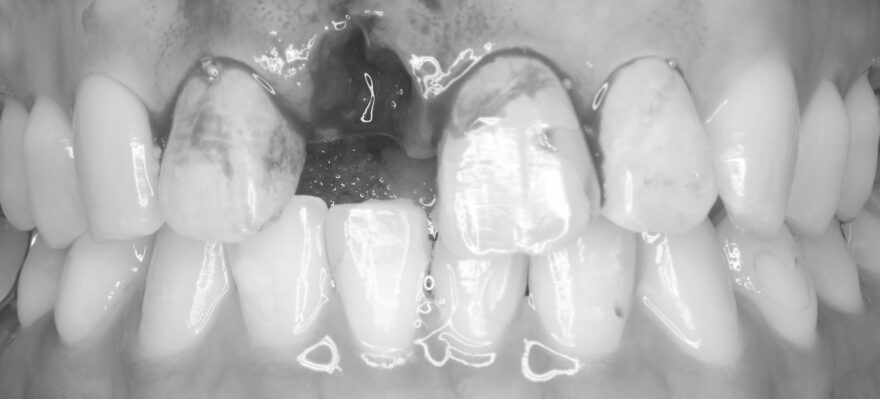

当院の診療メニューの中で最も自信があるのが、より自然な美しさを追求する前歯の審美インプラント治療です。

この中の1本が、インプラントで見た目の美しさと機能を復元した歯です。

自然に笑った状態で見える範囲においては、絶対にわからないと思います。

この段階でも分からない方がほとんどだと思います。